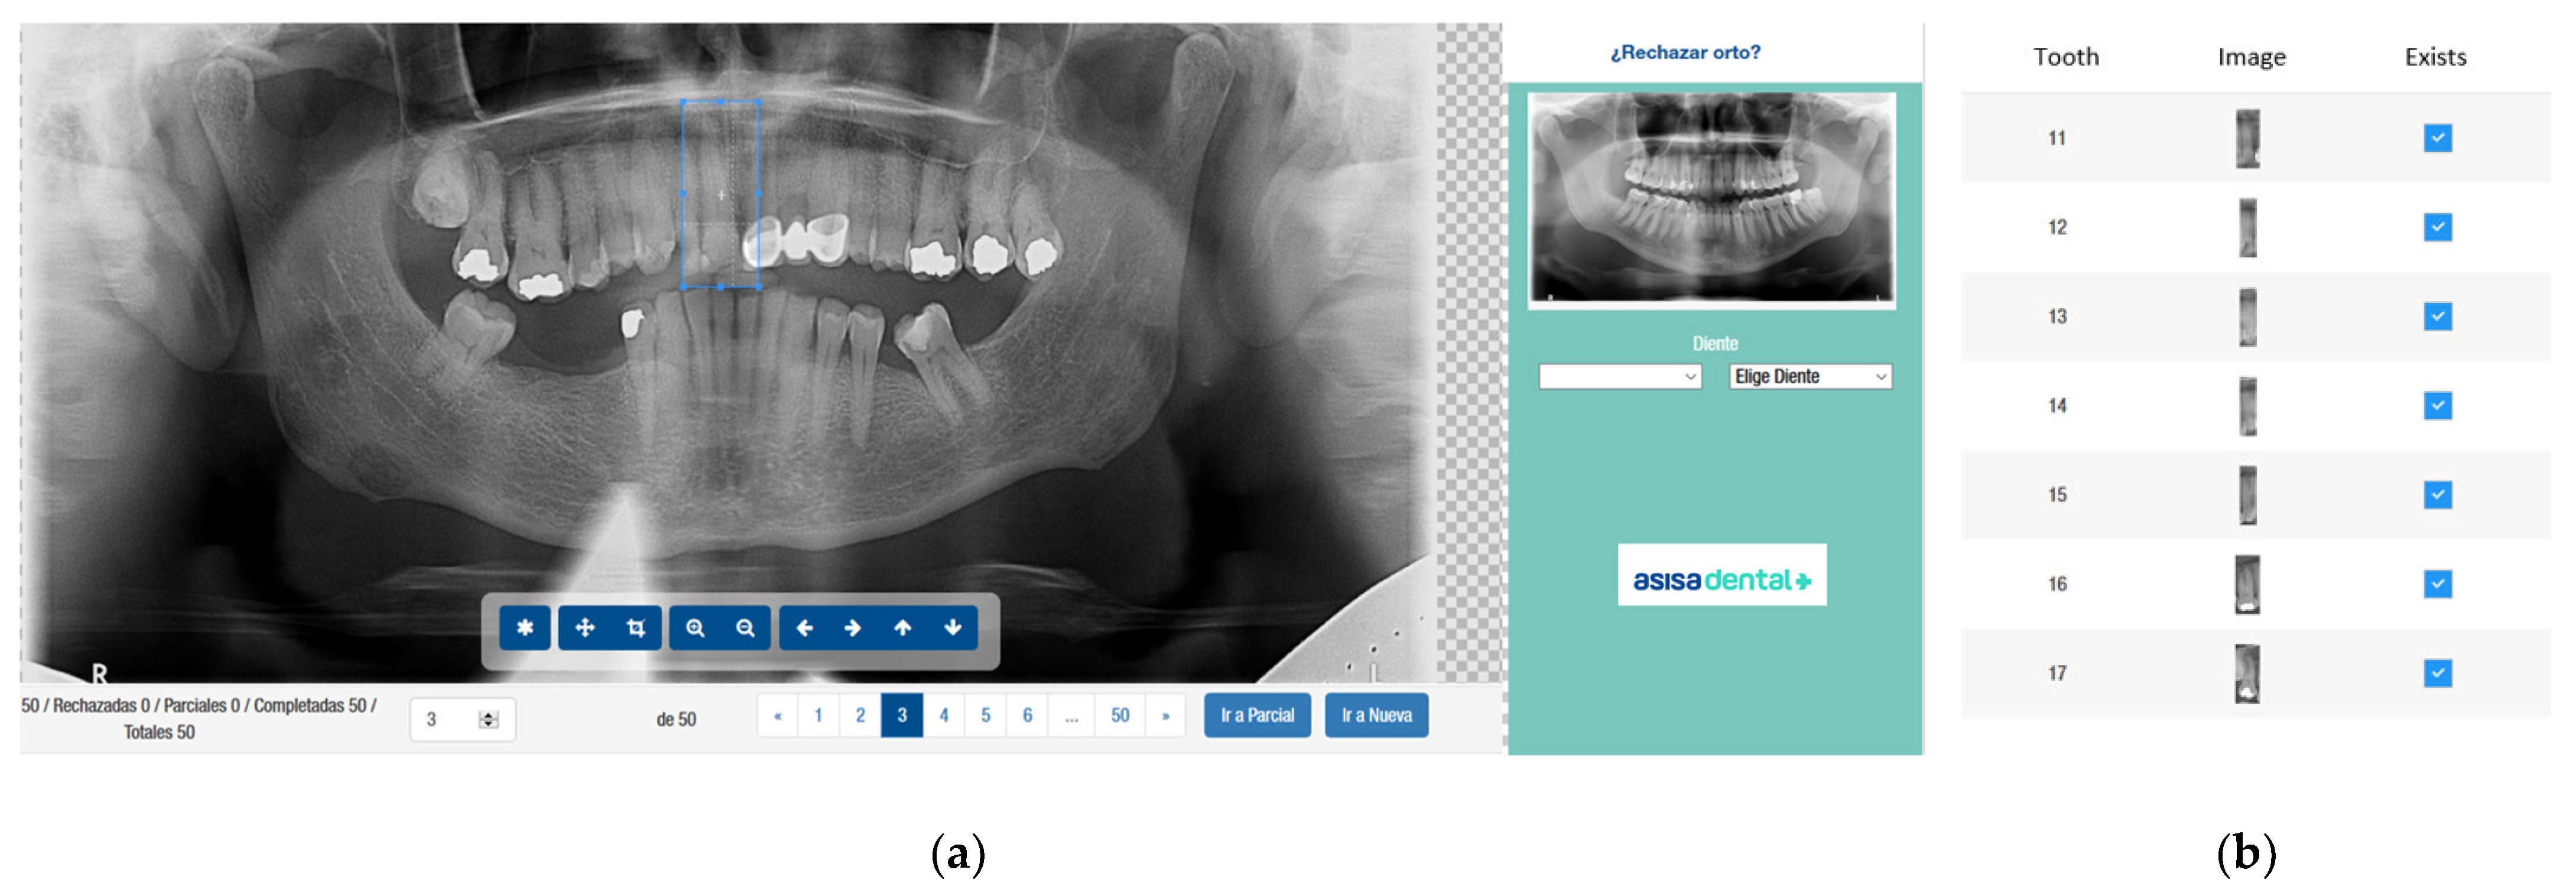

2.3. Image Categorization

2.4. Image Dataset

3.4. Model Execution Examples